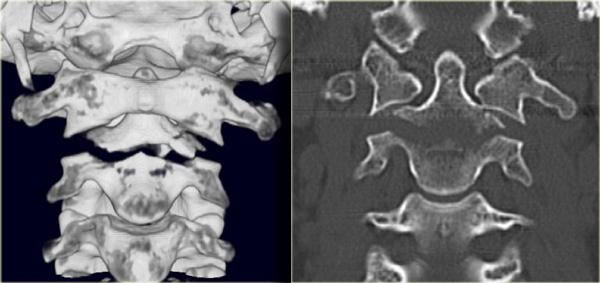

Hình bên trái là các lát cắt CT mặt phẳng coronal của một trường hợp gãy mỏm răng loại III khác.